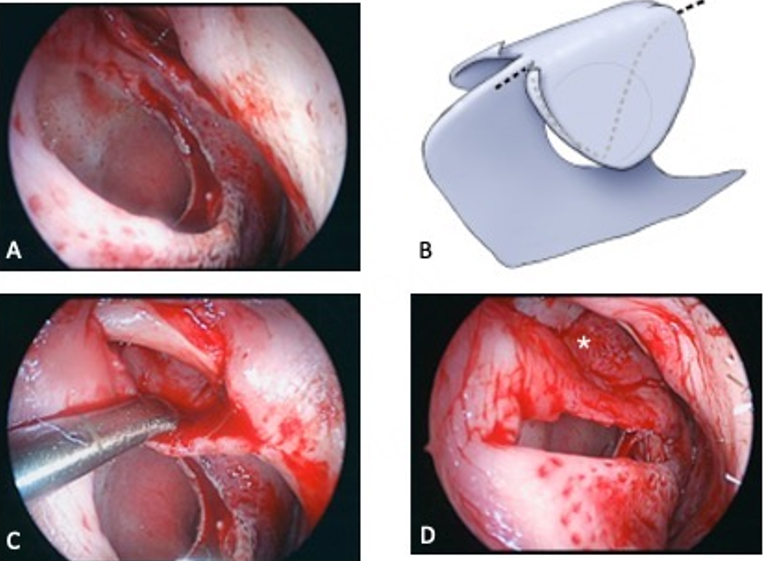

Complete tension-free closure on at least one side is a prerequisite for consistent success in perforation surgery utilizing mucosal flaps. The perforation repair procedure presented emphasizes complete coverage of the septal defect on the left side through the development and advancement of a superior bipedicled flap and, when necessary, an inferior bipedicled flap. The elliptical shape noted for most perforations conforms to a repair utilizing superior and inferior longitudinally oriented flaps. Flap incision placement and the need for an inferior flap are determined by several factors, most notably perforation position and size relative to nasal size. The left superior flap is the most consequential flap in this technique owing to its robust vascularity and thickness, as well as the degree of advancement that can be achieved compared to the inferior flap. Furthermore, mucosa from the undersurface of the ULC can be incorporated into the flap to increase width and achieve complete, tension-free defect coverage for relatively larger (vertical height) perforations and those that approach the internal valve angle[16] [Figure 5]. Prior rhinoplastic surgery, in which the upper lateral cartilages were separated from the septum, with or without spreader graft placement, interferes with the intact elevation of ULC mucosa utilizing an endonasal approach. An alternative, non-incisional technique that utilizes upper lateral cartilage mucosa has been described when using an open approach for the repair[5] [Figure 6].

Figure 5. Upper lateral cartilage mucosa (ULM) flap. (A) Endoscopic photo of 1.5 × 1.2 cm perforation and intercartilaginous incision; (B) Dashed lines depicting the extent of elevation and incisions connecting to dorsal septum incisions; (C) Endoscopic photo of elevation; (D) ULM flap advanced for suturing; Note the thin ULC mucosa (*) overlapping the superior cartilage margin.